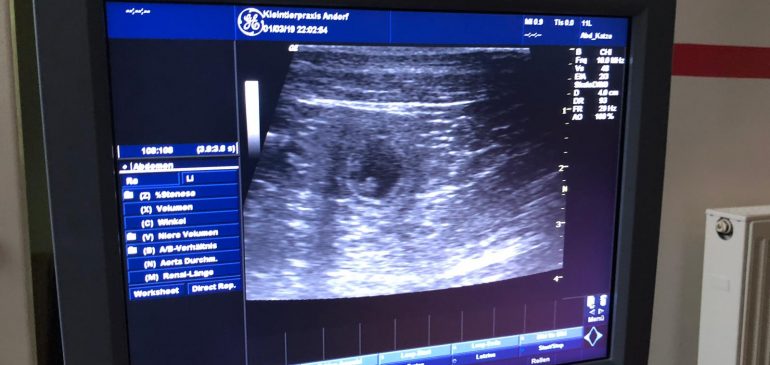

We are delighted to announce that the Valentines dates of Romeo „Diamante Blu Nella Mia Stanza“ and Siiri „Funstuff Flip A Coin“ apparently were successful. On the ultrasound we saw a bunch of puppies and many little hearts beating today so we hope for Funstuff I-litter to be born around…

We are so happy to announce that since 01.03.2019 we know that our Golden Retriever Girl Joey „Golden Mountain Spring’s Jollity“ is in whelp. If everything goes on as we hope, we are expecting our first Golden Retriever litter in the beginning of April. For more Information about this exciting…